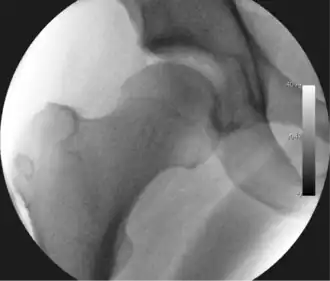

Figure 4. A needle is passed into the joint, breaking the 'suction seal', and allowing further distraction of the hip joint with minimal extra traction -

The next step is to insert a fine needle under x-ray guidance into the hip joint. This breaks the 'suction seal' of the joint and allows further distraction if necessary (see fig 4). The surgeon wishes to see the ball move out the socket by approximately 1 cm, so that access to the hip joint can be achieved with minimal risk of damage to the joint surfaces. Most surgeons will inject fluid into the joint at this stage, again to ensure that there is enough space between the ball and socket for safe instrument access. This needle is then removed. The next step is placement of the 'portals', or the small holes made to pass instruments into the joint. This is achieved by again passing a fresh hollow needle into the joint under x-ray control, usually in a slightly different position. The reason for this is so the surgeon can ensure that the needle, and subsequent cannulae do not penetrate and damage the acetabular labrum or cartilage joint surfaces (see fig. 5). Again, surgeons will have their own preferences as to their preferred placement. Through this hollow needle, a long thin flexible guide wire is passed into the joint, and the needle is removed over it, leaving the guide wire in situ. A small cut in the skin is made around the wire, to allow for larger cannulae to be placed over the wire through the portal. The wire therefore guides the larger cannulae into the joint. The most common external diameters of cannulae used are between 4.5 and 5.5 mm. Once the surgeon is satisfied that the cannula is in the correct position, by a combination of feel and x-ray guidance, the guide wire can be withdrawn. Once the first portal is correctly placed, any further portals may be created once the camera is in position, to ensure that they are placed with minimal risk to the joint surfaces. This process can be repeated to gain as many points of entry to the hip joint as the surgeon requires, normally between two and four. Certain of these entry points will be used for the viewing arthroscope and others for operating instruments.